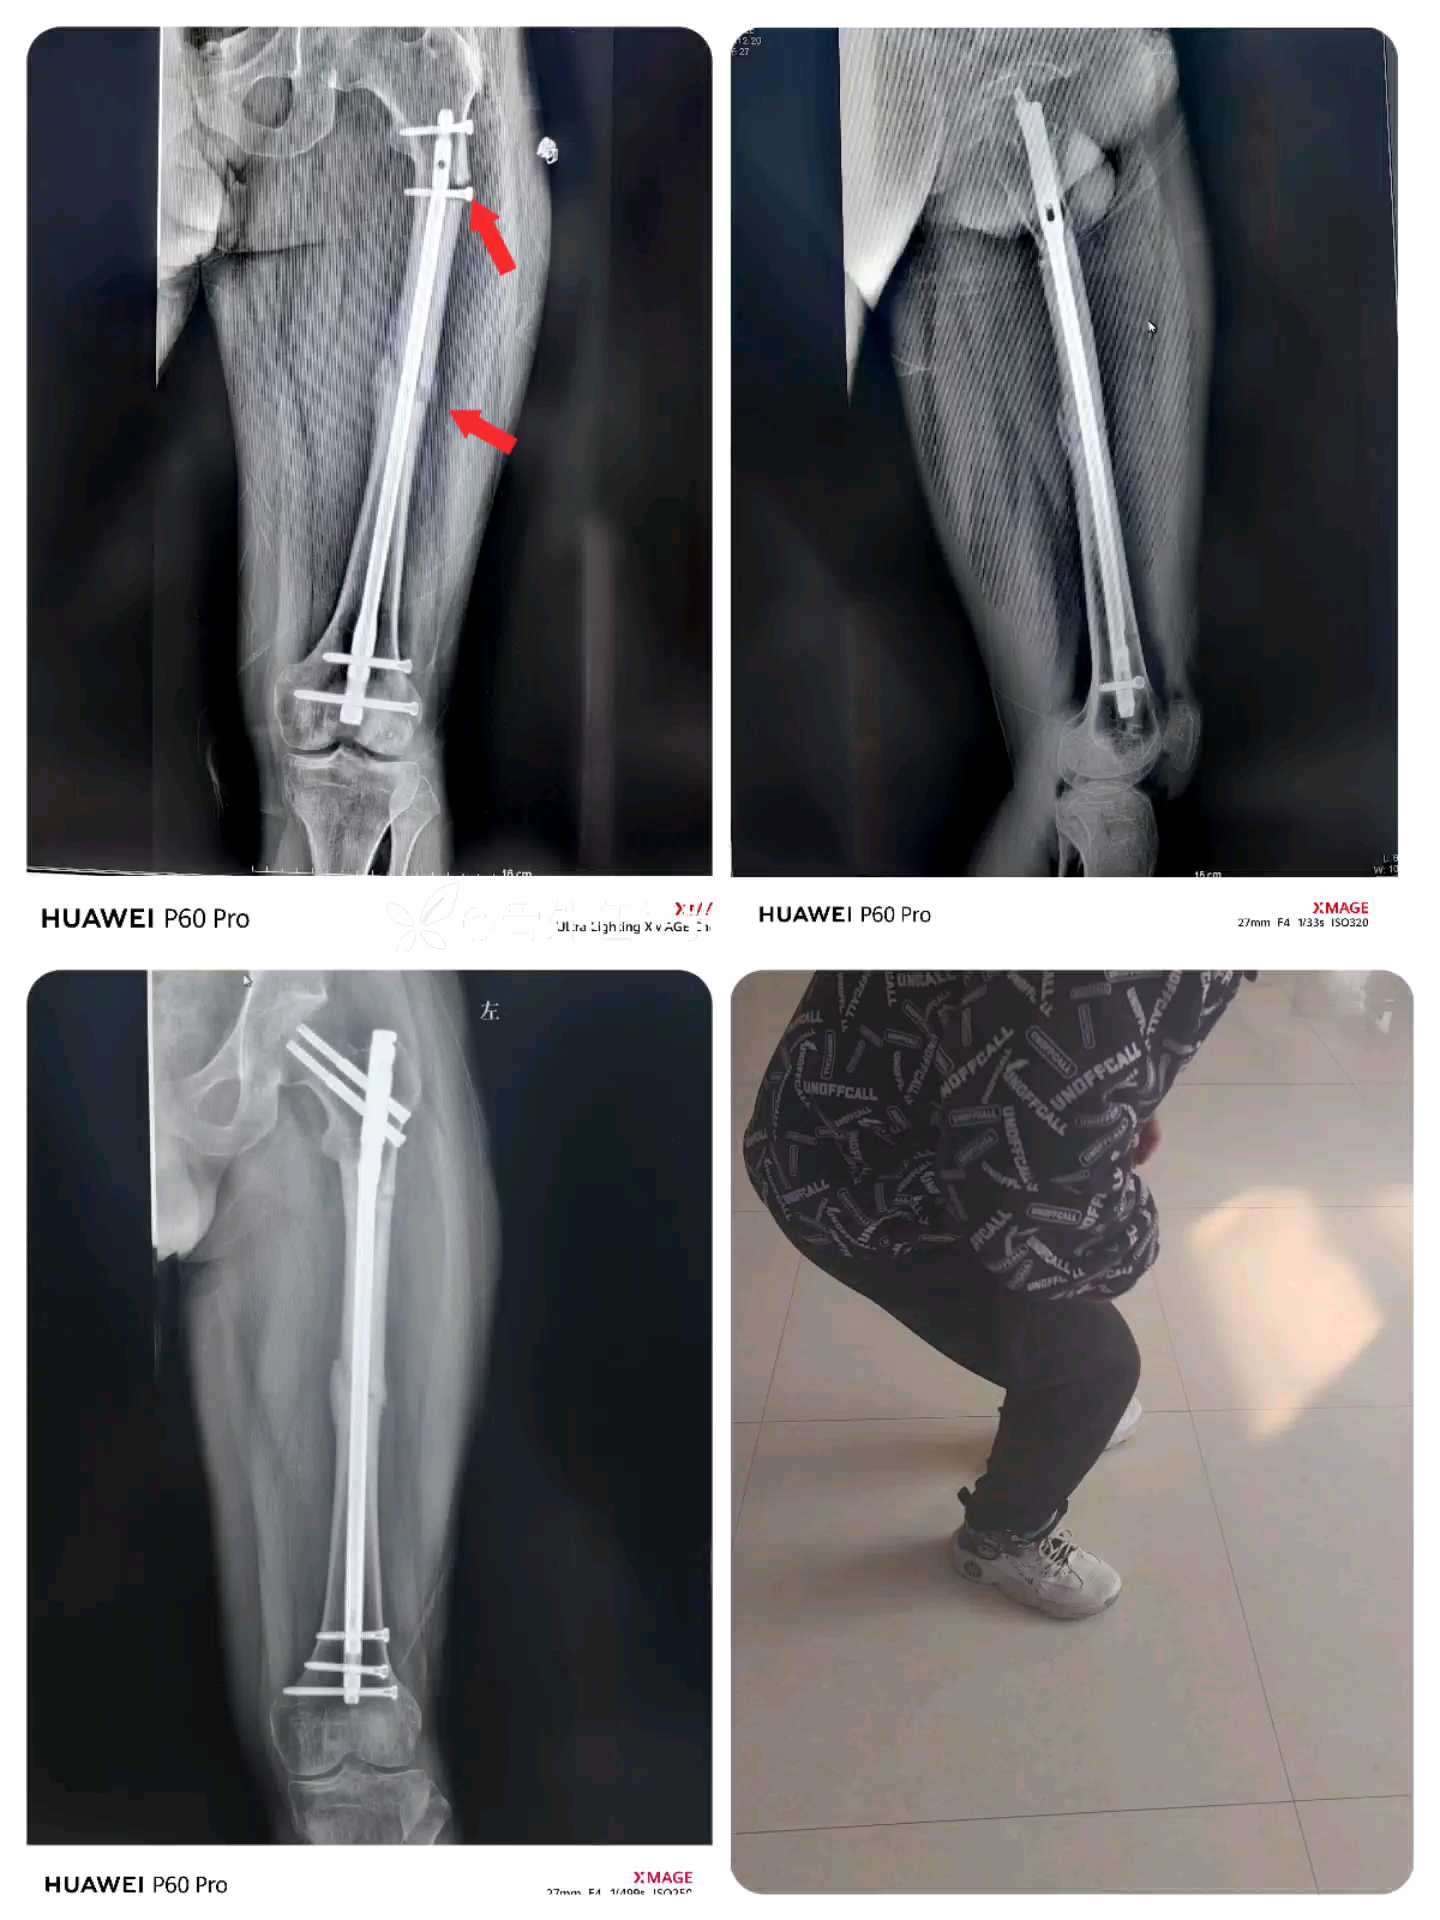

股骨干骨折“能顺行不逆行,能闭合不切开”——剩下的交给时间+康复锻炼。

患者性别:男

患者年龄:26岁

股骨干逆行髓内钉术后4个月,近端骨折

左股骨近端骨折

左股骨干骨折术后内固定存留

单纯取出逆行钉

中段骨折没有处理,

顺行,扩髓,粗髓内钉插入

术后3个半月复查

骨折愈合良好

膝关节活动良好

行走基本正常

已恢复正常工作,生活